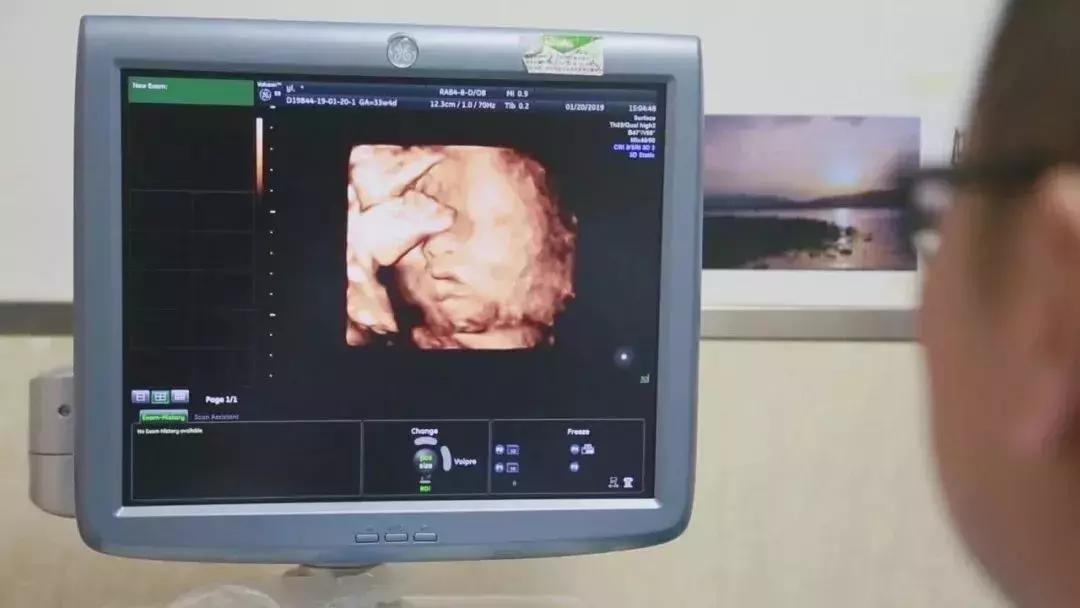

在对移植子宫连续监测后,为提高胚胎移植成功率,专家团队采取中西医结合的方法,改善杨华子宫内膜情况,为胚胎着床做好准备。2018年6月13日,妇产科王西林教授实时监测超声,在超声“慧眼”精确指引下,妇产科黄艳红教授小心翼翼地将冷冻胚胎植入移植的子宫内。

14天后,复苏胚胎着床,杨华成功妊娠,这已是第五次尝试。妊娠早期,杨华出现妊娠剧吐、先兆流产的症状,妊娠中晚期出现胎儿生长受限,先后4次住院进行保胎等治疗。

整个孕期,为避免出现并发症、确保母婴健康,妇产科、泌尿外科专家团队结合杨华身体情况,制定了个体化免疫抗排斥用药等方案,并定期进行超声、血药浓度、激素水平等监测。根据监测结果,实时调整用药,保证胎儿羊水、体重、胎心等生长发育指标处于正常范围。